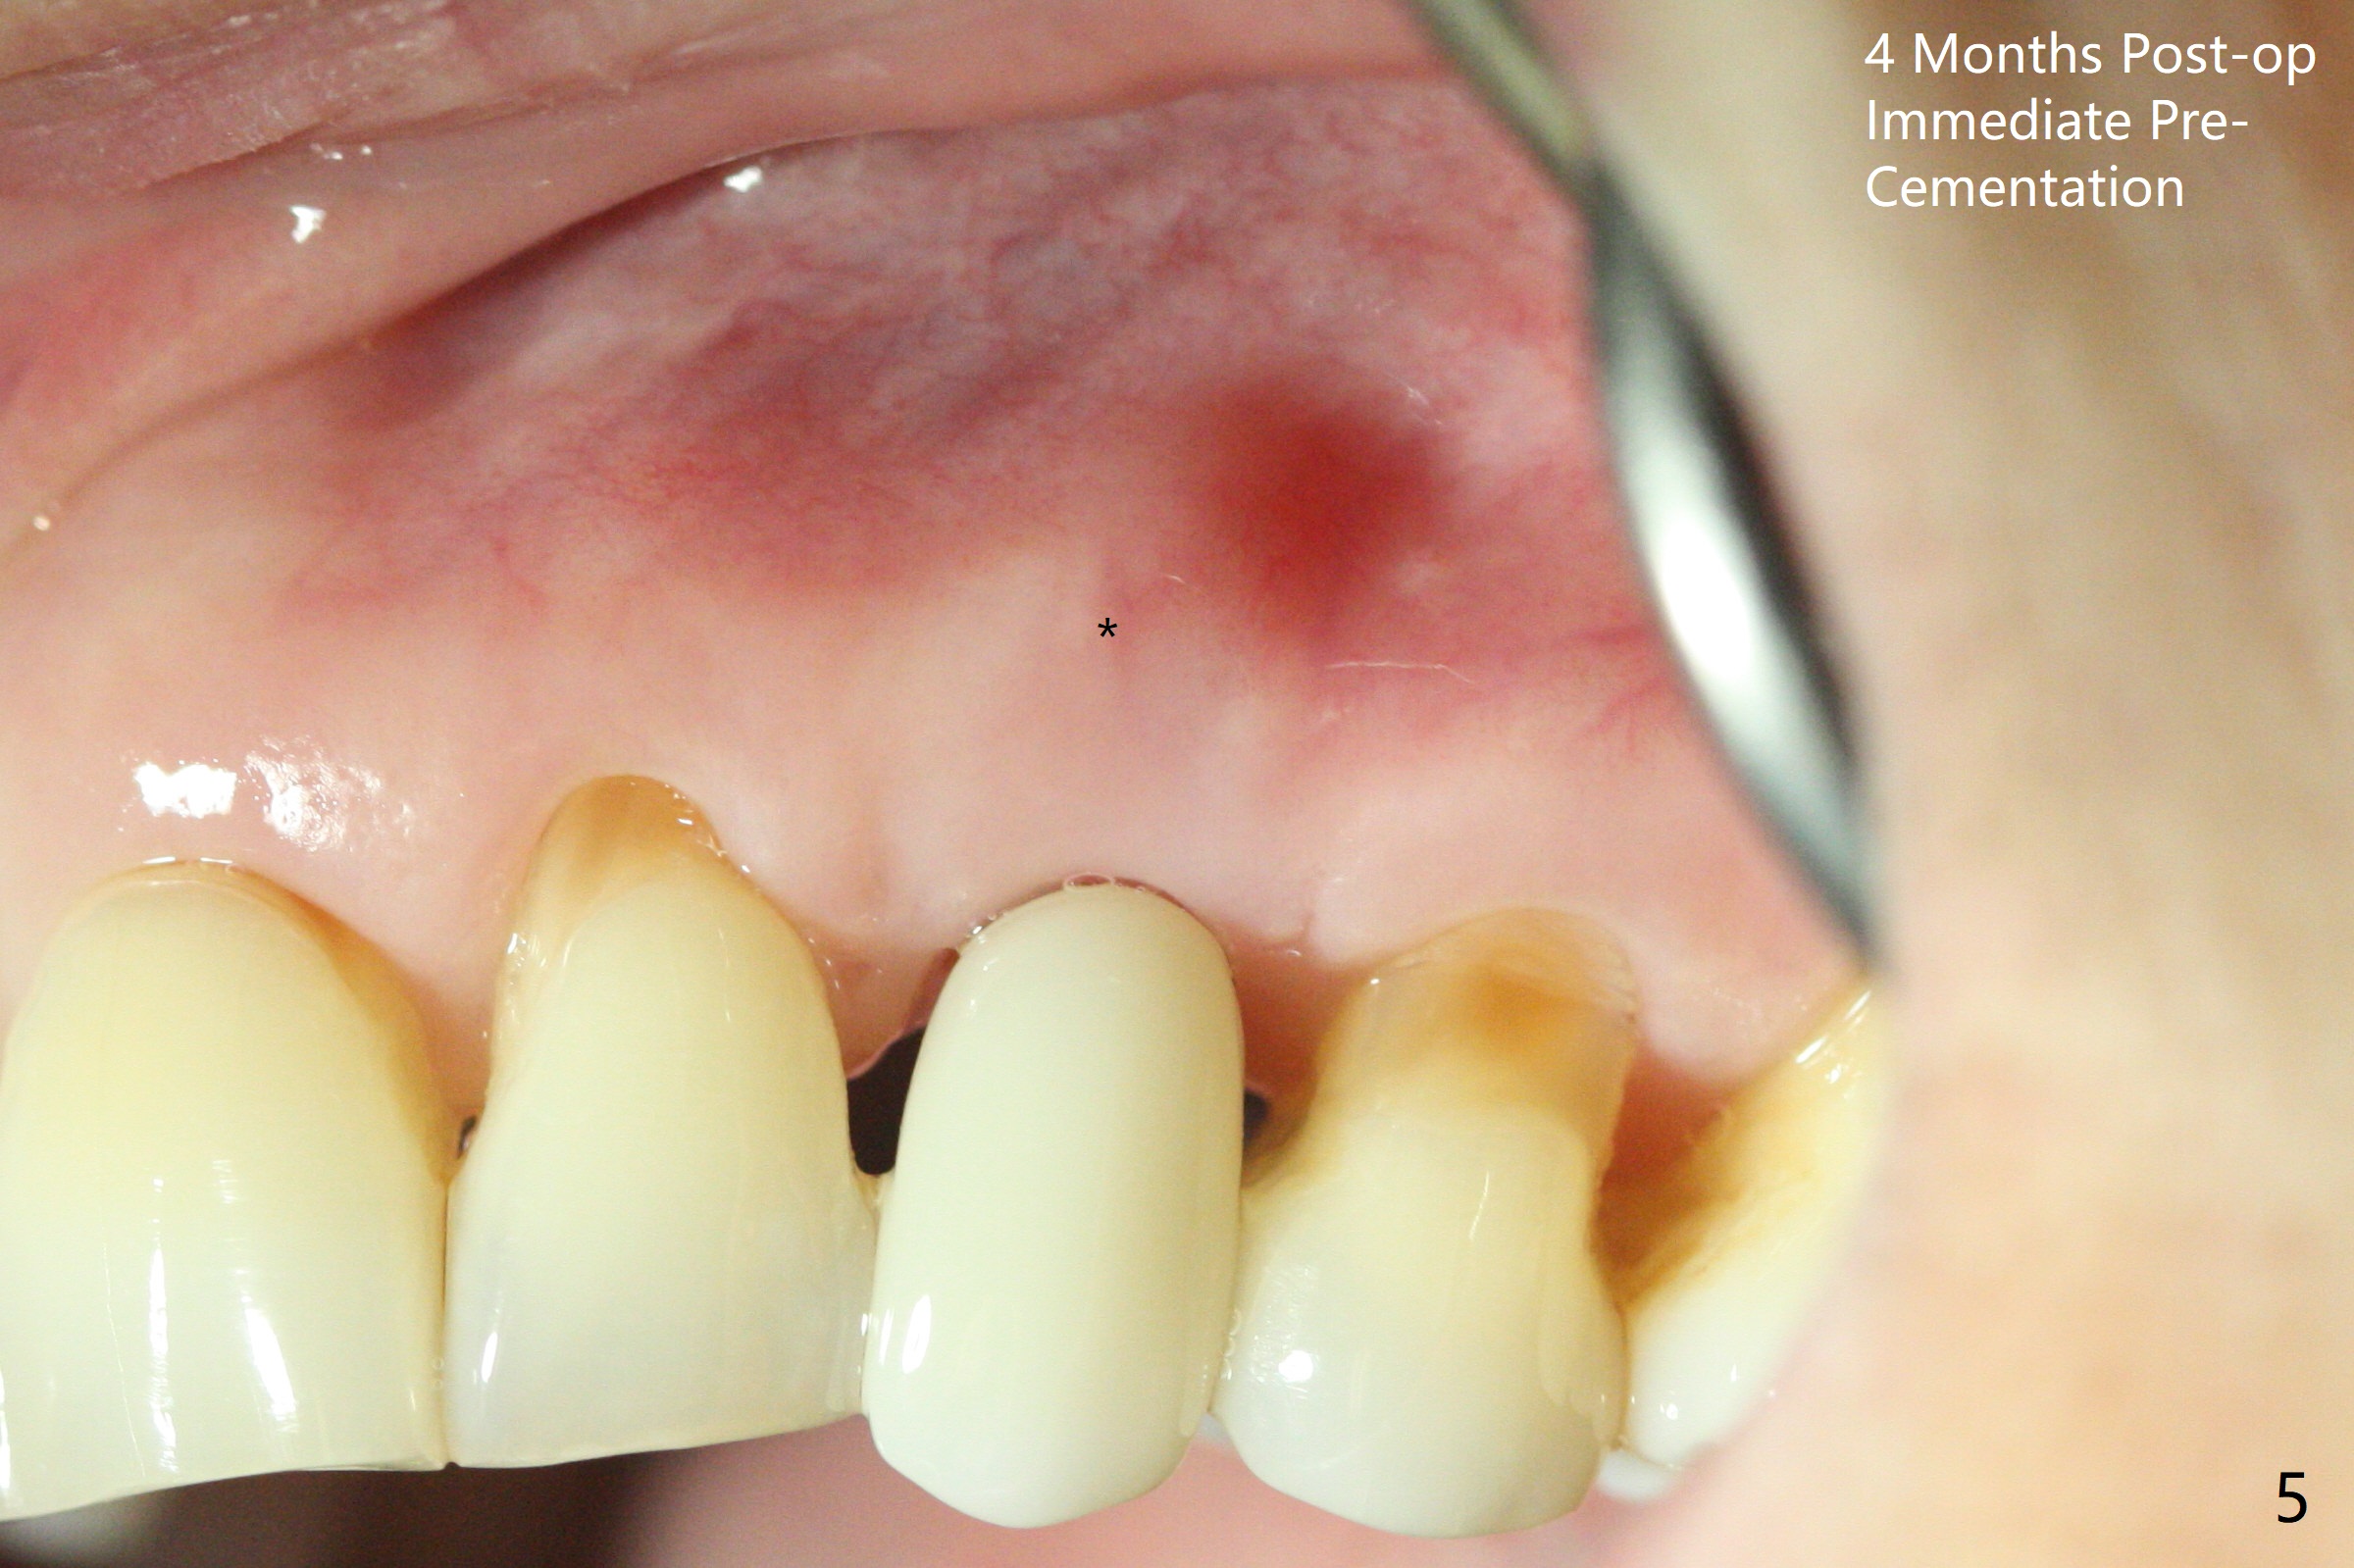

At surgery, the mesiodistal space for #11 is found to be narrow, 5 mm. To prevent buccal plate collapse, socket shield is planned. Due to limited space, incision is attempted so that the lower end of the shield (Fig.1 S) can be trimmed slightly subcrestal. It is also good for visibility for osteotomy (1.2 mm drill for 12 mm). A 2.5x14(2) mm 1-piece implant is placed with <35 Ncm (Fig.2,3 (*: allograft)). An immediate provisional is fabricated to the patient's satisfaction. There is no bone loss 3.5 months postop (Fig.4) or 4 months postop (Fig.5 *, corresponding to S in Fig.3). The recessive papillae are expected to reform to certain degree due to limited damage to the crestal bone.